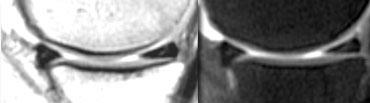

Ảnh PD và T2W. Tiền sử cắt sụn chêm một phần và khâu phục hồi. Khi nội soi khớp, không phát hiện rách.

Sụn chêm sau phẫu thuật 1

Trường hợp bên trái cho thấy sụn chêm có hình dạng bất thường cũng như tín hiệu bất thường chạm đến bề mặt trên ảnh PD nhưng không thấy trên ảnh T2W.

Bệnh nhân này có tiền sử cắt sụn chêm một phần và khâu phục hồi.

Dựa trên các phát hiện hình ảnh này, không thể xác định đây là rách hay là hình ảnh bình thường sau phẫu thuật.

Bệnh nhân này được phẫu thuật lại để tái tạo dây chằng chéo trước (ACL).

Phẫu thuật viên đã quan sát sụn chêm và xác nhận sụn chêm bình thường, tức là không có rách.